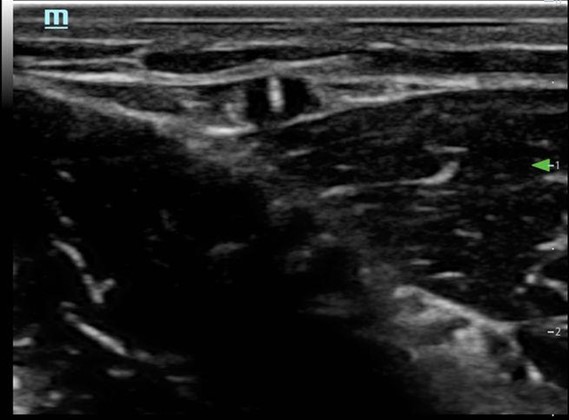

- Visualize the vein in cross-section (Fig. 3)

Figure 3. Short axis approach: vein visualized in cross axis